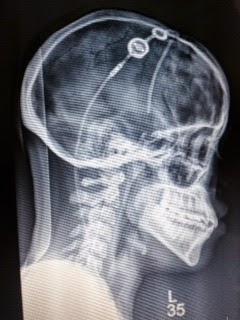

Correct shunt placement 2014 to present

On March 6 I had my anticipated shunt revision surgery.  In 2009, my shunt had been placed on the wrong side of my brain by a different doctor.  During the surgery (2014) my shunt stopped working because it had been on the wrong side for 5 years. The ventricular catheter was leaking csf fluid all over my brain. While the surgeon was replacing my shunt valve, I had a 10 millimeter intracranial brain hemorrhage on the left side of my brain. The bleed led to a hemorrhagic stroke by my brain stem which was followed by a traumatic brain injury.

When the catheter was returned to the right side of my brain, I had a 5 millimeter intraparenchymal

brain hemorrhage.